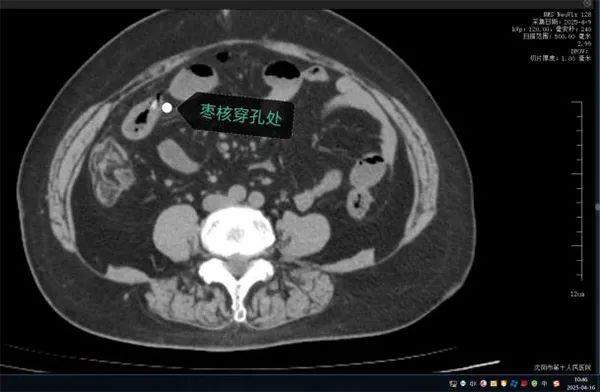

案例二:刺穿小肠 生死一线

无独有偶,63岁的康阿姨近日因突发“刀绞般”剧烈腹痛,深夜被紧急送往沈阳市第十人民医院。短短数小时内,她出现高热、腹肌强直等弥漫性腹膜炎症状。CT检查显示腹腔游离气体,高度怀疑消化道穿孔。

家属回忆,当天上午康阿姨吃粽子时误吞两颗枣核。医生会诊判断枣核尖端已刺穿小肠,紧急手术取出异物。